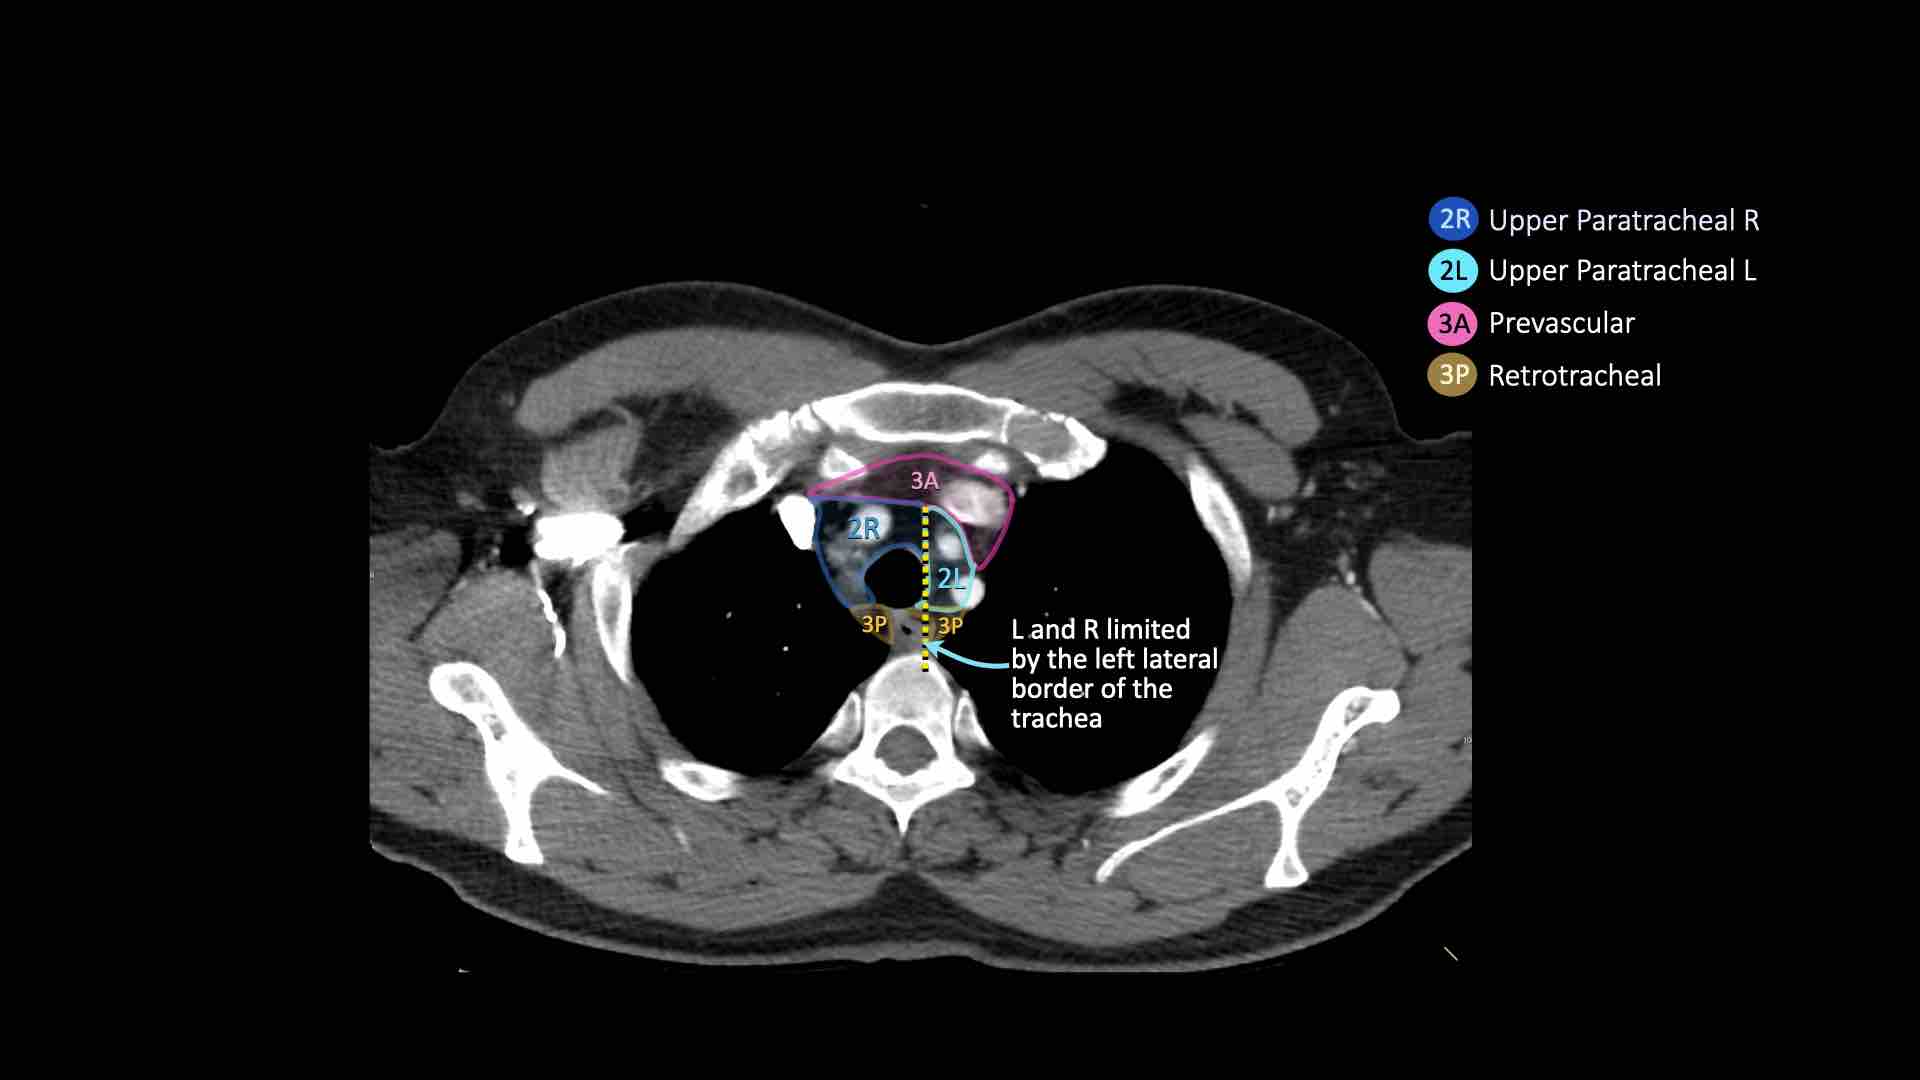

Hạch nhóm 2R trải dài đến bờ bên trái của khí quản.

Hạch nhóm 2L nằm ở phía trái của bờ bên trái khí quản.

2R. Hạch cạnh khí quản trên bên phải

2L. Hạch cạnh khí quản trên bên trái

Bên trái là hạch nhóm 2 nằm phía trước khí quản, tức là hạch 2R.

Ngoài ra còn có một hạch trước mạch máu nhỏ, tức là hạch nhóm 3A.

- Cạnh khí quản trên: phía dưới xương đòn, bên phải nằm trên giao điểm của bờ dưới tĩnh mạch vô danh (tĩnh mạch tay đầu trái) với khí quản, bên trái nằm trên cung động mạch chủ

- Trước mạch máu và Sau khí quản: nằm trước các mạch máu (3A) hoặc trước cột sống (3P)